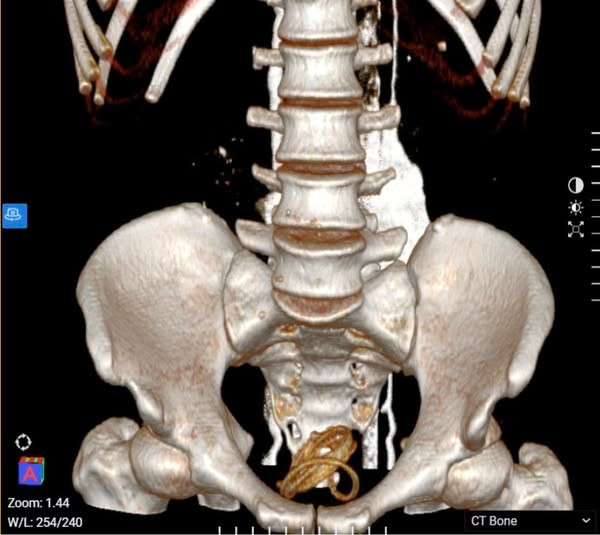

Hình ảnh chụp cắt lớp vi tính dị vật trong bàng quang của bệnh nhân. Ảnh BV

Kết quả thăm khám và chụp cắt lớp vi tính ổ bụng cho thấy bàng quang của bệnh nhân chứa dị vật kèm nhiễm khuẩn niệu. Các bác sĩ đã tiến hành điều trị kháng sinh nhằm kiểm soát nhiễm khuẩn. Tiếp đó, bệnh nhân được tiến hành nội soi bàng quang để lấy dị vật ra ngoài. Đoạn ống cao su dài khoảng 1 mét, đường kính 3mm, bề mặt đã bám nhiều cặn sỏi do tồn tại trong môi trường nước tiểu đã được ê-kíp các bác sĩ lấy ra thành công.